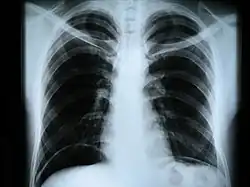

Рентгенограмма органов грудной клетки в прямой проекции. Видно скопление воздуха под куполами диафрагмы.

• рентгенография грудной клетки — инфекционные, опухолевые и другие заболевания,